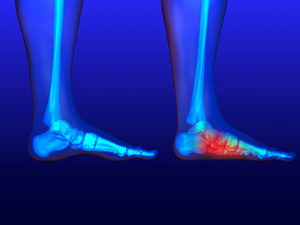

A stress fracture may gradually develop from frequently participating in running and jumping activities, and can be uncomfortable. Effective treatment for this type of injury generally begins with ceasing the activity that caused the pain, and wearing a boot or cast that will help to provide the support that is necessary as the healing process occurs. Prevention of further stress fractures may be accomplished by warming up properly before running, and gradually increasing the intensity of your physical activity. It is suggested that a podiatrist be consulted who can offer you preventative and treatment options.

Stress fractures occur in the foot and ankle when muscles in these areas weaken from too much or too little use. The feet and ankles then lose support when walking or running from the impact of the ground. Since there is no protection, the bones receive the full impact of each step. Stress on the feet can cause cracks to form in the bones, thus creating stress fractures.

Pain from the fractures occur in the area of the fractures and can be constant or intermittent. It will often cause sharp or dull pain with swelling and tenderness. Engaging in any kind of activity which involves high impact will aggravate pain.